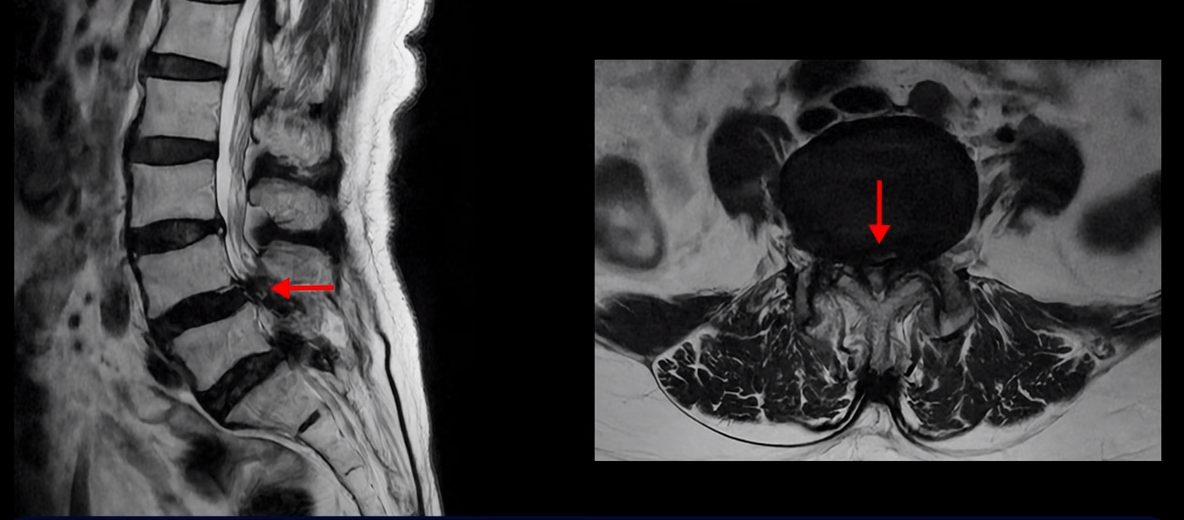

먼저 이분 MRI를 보면서 자세히 설명 드리겠습니다. 보시다시피 허리 여러 마디가 안 좋습니다.

특히 4번 5번에는 심한 중심성 협착이 있어 척추관이 매우 좁아져 있습니다.

5번 1번도 척추관이 좁아져 있고 특히 좌우 신경이 빠져나가는 추간공이 좁아져 있는데 5번 1번 왼쪽 추간공은 많이 좁아져서 신경이 눌리고 있습니다.

그래서 이 환자분은 허리도 아프지만 양쪽 엉덩이가 저리고 아프며 양쪽 다리가 무거워서 걷기가 어렵고 양쪽 발바닥까지 자갈을 밟는 것 같은 감각 이상이 있습니다. 신경이 많이 눌리니까 양쪽 다리에 힘이 없어 작년부터 지팡이를 짚으셨는데요. 우리나라 최상급 대학병원에서도 고령이시고 여러 마디가 안 좋으시니 큰 수술을 받는 것보다 그냥 조심하면서 참고 사시는 게 더 낫다고 말씀을 들었습니다.